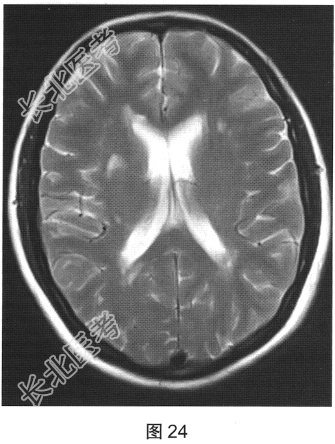

患者女性,40岁,渐进性肢体无力6个月。颅脑MRI检查如图23、图24所示。

- 多项选择题1.根据MRI表现,可能的诊断是( )

A、多发脑缺血

B、脑白质病变

C、脑白质稀疏

D、脑萎缩

E、多发性硬化

F、脑炎